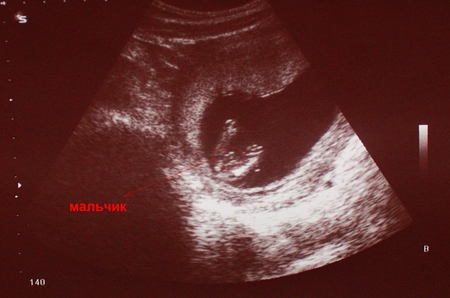

А здесь мы уже не скрываем свой пол:

Мы очень ждем тебя наш малыш!!!!

А имя мы уже очень давно выбрали Даниэль!